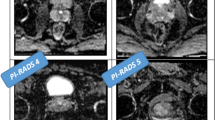

Prostate cancer represents the most common cancer afflicting men. It may be asymptomatic at the early stage. In this paper, we propose a methodology aimed to detect the prostate cancer grade by computing non-invasive shape-based radiomic features directly from magnetic resonance images.

We use a freely available dataset composed by coronal magnetic resonance images belonging to 112 patients. We represent magnetic resonance slices in terms of formal model, and we exploit model checking to check whether a set of properties (formulated with the support of pathologists and radiologists) is verified on the formal model. Each property is related to a different cancer grade with the aim to cover all the cancer grade groups.

The experimental analysis demonstrates the effectiveness of radiomics and formal verification for Gleason grade group detection from magnetic resonance.